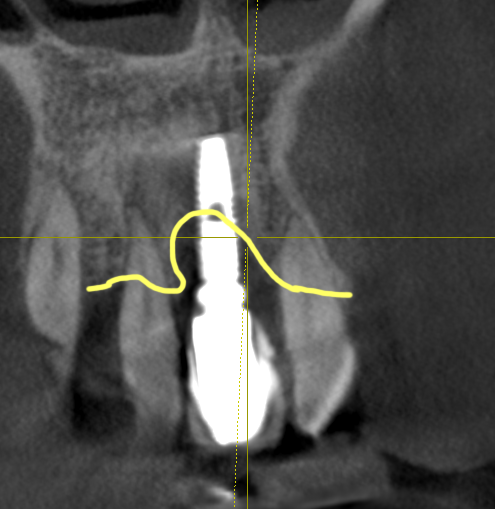

이 환자분은 40대의 젊은 남성이었는데 아무래도 치아가 하나둘 망가지면서 관리를 포기한 상태였던 거 같습니다. 입 안에 임플란트가 앞니에 하나 있었는데 해당 임플란트는보기에 흉하게 만들어져 있을 뿐 아니라 이미 임플란트주위염이 생겨져 있어서 해당 임플란트도 다른 치아처럼 제거를 하기로 했습니다.

이 분은 치주염이 심했지만 다행히 임플란트 식립을 하기 위한 가용골이 적절히 있었고, 간단한 뼈이식을 일부 하는 정도로 모든 임플란트를 식립할 수 있었습니다. 그리고 임플란트의 위치도 대체적으로 적절한 위치에 식립한 가능한 상태였습니다. 뼈가 불규칙하게 파괴되는 경우에는 임플란트의 상하위치가 좋지 않게 되는 경우도 있지만 이 분의 경우에는 적절히 좋은 위치에 가능했습니다.